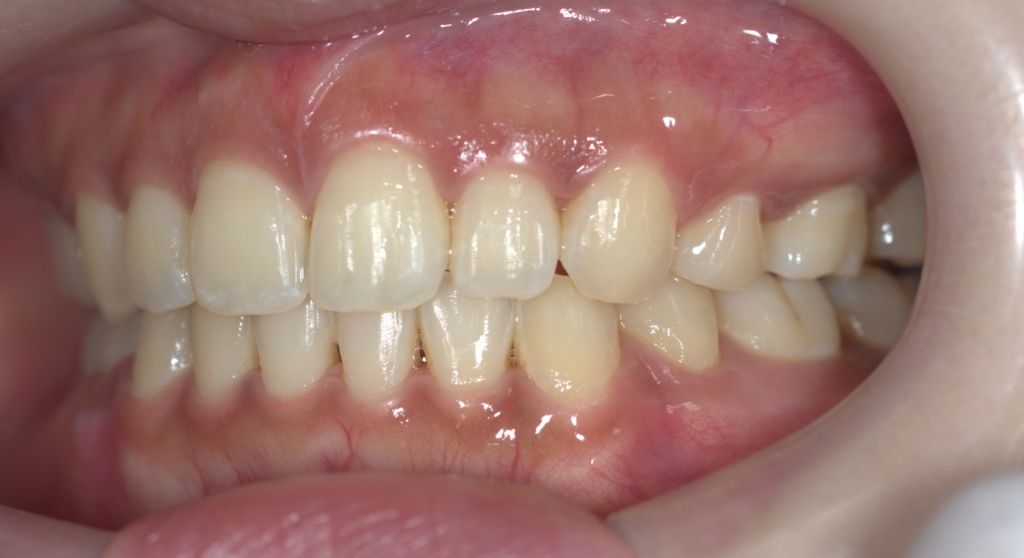

【After】

矯正後の状態をレントゲン写真で確認すると、

左側が矯正治療前、右側が矯正治療後

オトガイ部にあった梅干し状のシワがほぼ無くなったことが分かります。

矯正後は口元がとてもスッキリしたことが見て取れると思います。